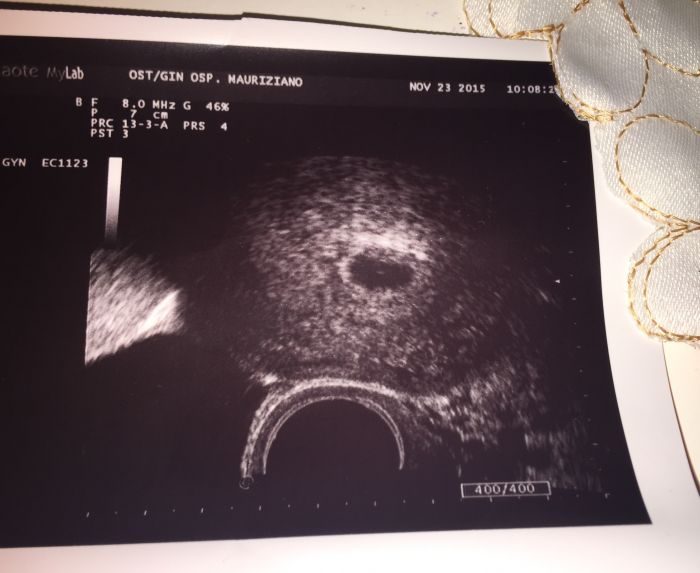

Ja byla dnes na pohotovostipodle ms 5+2 a je videt jen dutinka a zloutkovej vacek dalsi uzmam pristi ctvrtek

Ja mela ovulku 14 den od menzes takze dnes je to 23 dni od ovulace